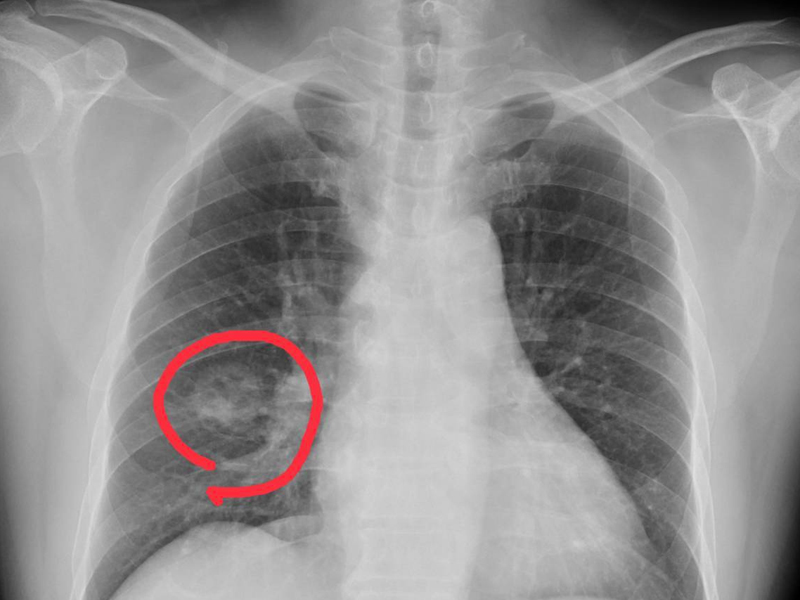

一談及癌症,絕大多數人的腦海中會即刻浮現出極為可怕的景象:瘦骨嶙峋、周身疼痛難忍、生活無法自理 ... 然而,事實果真如此嗎?答案是否定的。 我這般回答,想必會有人提出異議。反對者分為兩類:其一為正在承受癌症痛苦的病人及其家屬,或者目睹過癌症病人痛楚的人;其二則是既非病人或家屬,也未真正見過癌症病人或踏入過腫瘤科病房,只是想當然地認為癌症乃絕症,必然極度痛苦。前一類人的反對完全可以理解,畢竟他們所見確為事實,不少癌症病人的確飽受各種痛苦;而後一類人則是無端湊熱鬧,屬於沒有發言權卻硬要發聲之人。 癌症病人固然可能承受各式各樣的痛苦,但不能就此斷言,得了癌症就必定會有痛苦表現。實際上,即便處於癌症晚期,也仍有可能毫無痛苦表現,甚至可能毫無病狀。 常有癌症病人或家屬詢問:為何癌症都已晚期,卻毫無癥狀? 由於他或其家人被查出癌症且已是晚期,卻無癥狀,這令他們深感困惑。在多數人看來,癌症怎會無癥狀,尤其癌症晚期更不應無癥狀,難道是誤診? 為何癌症都已晚期,卻仍無癥狀?下面為大家剖析一番。 無論是早期還是晚期癌症,癥狀並非必然出現。早期可能無癥狀,這易於理解,因癌症尚局限,未擴散轉移。然而,晚期癌症已擴散轉移,怎會無癥狀?這着實令人費解。 多數人認為癌症晚期必定有顯著癥狀,通常而言,此觀點確實沒錯,但判斷癌症早期或晚期並非僅依據癥狀。 首先需明白,癥狀因何出現? 所謂癥狀,即身體不適的表現,如疼痛、咳嗽、腹脹、腹瀉、吞咽困難、呼吸困難等等。之所以出現這些不適,本質上是因為癌症侵犯、壓迫或破壞了某個器官組織,從而產生相應表現。例如,氣管有腫瘤侵犯或壓迫,便會咳嗽;食管長了腫瘤堵塞食管,進食時就會有吞咽困難;胸腔有胸水可能壓迫肺,就會氣喘呼吸困難;有腹水則可能有腹脹表現。由於癌症可能侵犯或轉移至全身任何部位(除毛髮和指趾甲外),所以癌症病人可能有任何可能的癥狀。但關鍵在於,一人確診癌症時,其癌症或許尚未導致相應組織器官出問題從而產生癥狀。癌症病人可能有各種表現,但不等於必然有癥狀,不可混為一談。 顯然,早期癌症也可能侵犯或壓迫臟器組織從而出現癥狀,但這種幾率相對較小,因早期癌症侵犯較淺或較小,不易對周圍組織器官產生明顯影響。而晚期癌症通常體積較大、侵犯較深或已轉移至其他部位,從而更易出現癥狀。 可見,是否出現癥狀,主要並非取決於癌症處於早期還是晚期,而是與腫瘤的部位、大小等有關,即是否影響了相應的組織器官。 晚期癌症若未對周圍組織器官造成影響,或者雖有遠處轉移但並非重要臟器,比如僅轉移至淋巴結或皮下,或許就不會有明顯不適。而有的早期癌症之所以為早期,腫瘤本身可能不小,或者其生長部位特殊,就可能有明顯癥狀,甚至有的良性腫瘤(比如腦內的良性腫瘤)可能出現明顯癥狀乃至危及生命(腦幹的良性腫瘤可能壓迫呼吸心跳中樞而致命)。 良性腫瘤、早期癌症、晚期癌症,都可能出現癥狀,也都可能無癥狀,差別僅在於出現癥狀的概率大小。良性腫瘤出現癥狀的概率較小,早期癌症出現癥狀的概率次之,晚期癌症出現癥狀的概率最大,但不等於良性腫瘤和早期癌症一定無癥狀,不等於晚期癌症一定有癥狀。 事實上,不少晚期癌症是在無意之中被發現的,即毫無癥狀,是在體檢時偶然察覺的,不能僅憑藉癥狀來判斷是否患癌、是早期還是晚期。 不過,必須清楚,儘管有的晚期癌症暫時無癥狀,但這只是暫時、階段性的,隨着癌症的持續發展,最終必然會出現癥狀,不會始終無癥狀。 小結: 1. 良性腫瘤一般無癥狀,但也可能有癥狀,甚至嚴重癥狀,甚至威脅生命。 2. 早期癌症多數無癥狀或癥狀輕微,但也可能有明顯癥狀。 3. 晚期癌症通常有癥狀,或輕或重,但也可能無癥狀,不過晚期癌症的「無癥狀」只是暫時、階段性的,遲早會有癥狀出現。 |